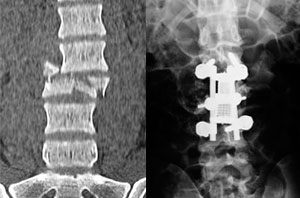

Casos Complejos 1

Varón de 35 anos, accidente de transito. Operado en primeras 24 horas con reconstrucción total de columna con uso de tornillos y reemplazo de cuerpo vertebral de vertebra fracturada. Presento recuperación total de lesión neurológica inicial.